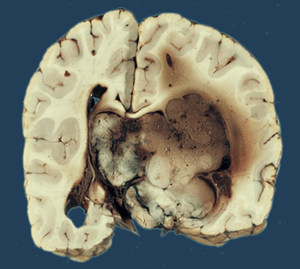

Choroid plexus papilloma, also known as papilloma of choroid plexus, is a rare benign neuroepithelial intraventricular WHO grade I lesion found in the choroid plexus.[1] It leads to increased cerebrospinal fluid production, thus causing increased intracranial pressure and hydrocephalus.[2]

Choroid plexus papilloma occurs in the lateral ventricles of children and in the fourth ventricle of adults. This is unlike most other pediatric tumors and adult tumors, in which the locations of the tumors is reversed. In children, brain tumors are usually found in the infratentorial region and in adults, brain tumors are usually found in the supratentorial space. The relationship is reversed for choroid plexus papillomas.